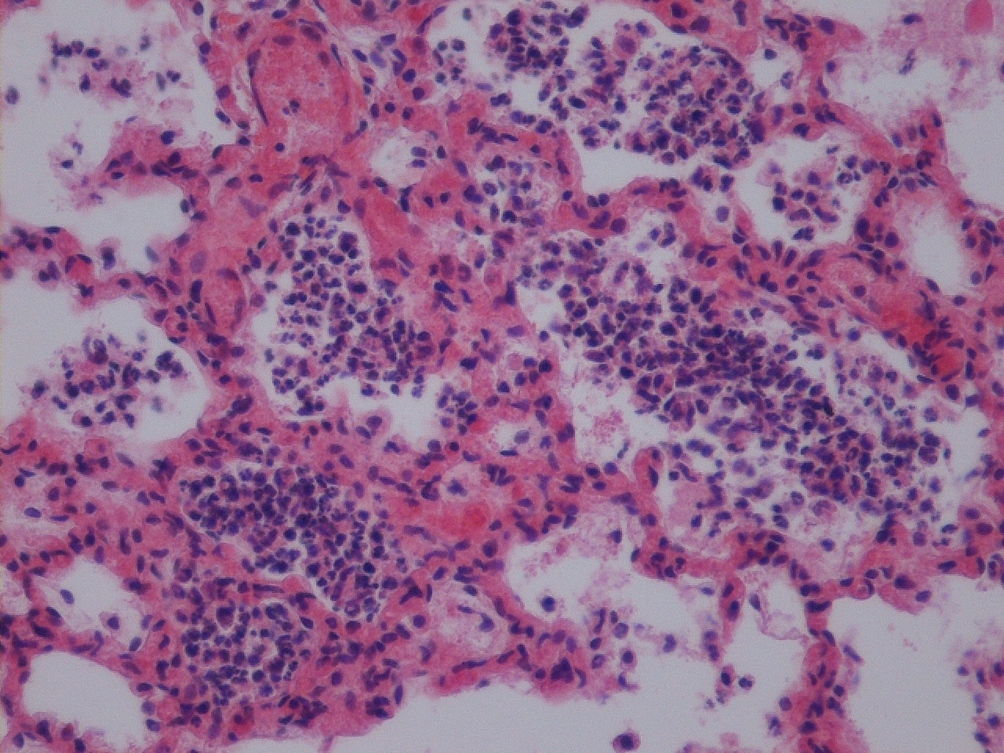

In this article a case of septicaemia, caused by Brevundimonas vesicularis in a newborn pygmy goat with congenital goitre, is described. B. vesicularis is an aerobic non-sporulating non-fermenting motile Gram-negative bacillus, ubiquitous in the environment. It is susceptible to aminoglycosides and anti-pseudomonal penicillins and resistant to ampicillin and cephalosporins. To date, B. vesicularis has been isolated from water, soil, plants and several human clinical specimens, mostly in immunosuppressed patients causing endocarditis, arthritis, keratitis and septicaemia. It has never been reported to cause any problems in animals. A newborn pygmy goat kid died 18 hours after a normal parturition. Prior to death, no clinical abnormalities were observed, the kid was normally developed, in good condition and had a normal suckling reflex. At necropsy, a severely enlarged thyroid gland, an acute embolic pneumonia, acute catarrhal enteritis and a moderate splenomegaly were noticed. Microscopically, severe thyroid gland hyperplasia, embolic pneumonia and catarrhal enteritis were confirmed. In the liver and myocardium small multifocal necroses, surrounded by single neutrophils, were noticed. A severe diffuse lymphoreticular hyperplasia was diagnosed in the spleen and a diffuse parenchymatous degeneration was noticed in the kidneys. Numerous small colonies of Gram-negative bacteria were observed in the liver and lungs. Intensive growth of smooth, thick, convex, yellowish colonies on blood agar and green colonies on Drigalski agar was obtained from the liver, spleen and lung samples. The bacteria were identified as B. vesicularis by a commercial kit. The bacterium resulted sensitive to broad-spectrum antimicrobial agents, including ampicillin, cefotaxime, ceftriaxone and ceftazidime-clavulanate. To the best of our knowledge, this is the first report of B. vesicularis septicaemia in animals. Weak immunodeficient goitrous kids are predisposed to many bacterial infections, including the ubiquitous and opportunistic B. vesicularis, which can cause fulminant septicaemia and death within a few hours after birth.